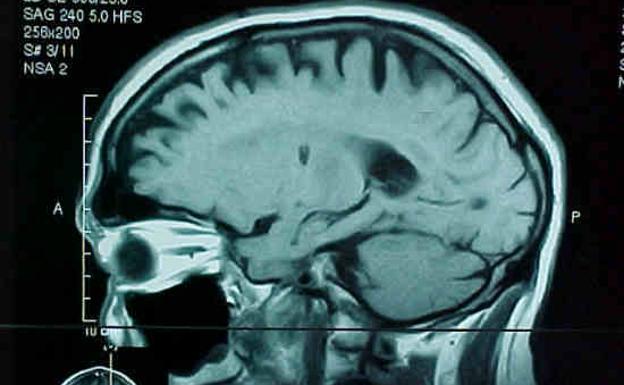

Investigadores españoles han comprobado en ratones la efectividad de estos nuevos fármacos que actúan sobre las proteínas que desarrollan los tumores